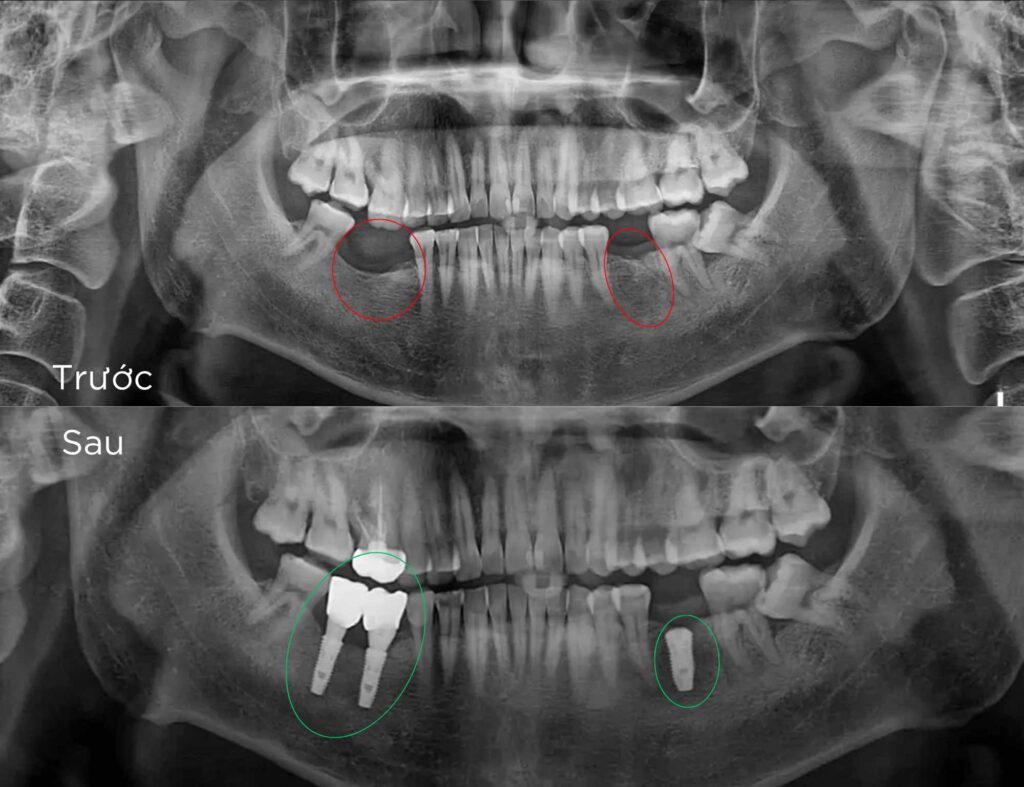

Trồng Implant vài răng

Trồng răng Implant vài răng

để phục hồi răng và tái tạo hình dáng của các răng đã mất. Là giải pháp tối ưu cho những người mất từ hai răng trở lên, giúp khôi phục khả năng ăn nhai, cải thiện thẩm mỹ và ngăn ngừa các vấn đề do mất răng gây ra, như tiêu xương hàm hay lệch khớp cắn.